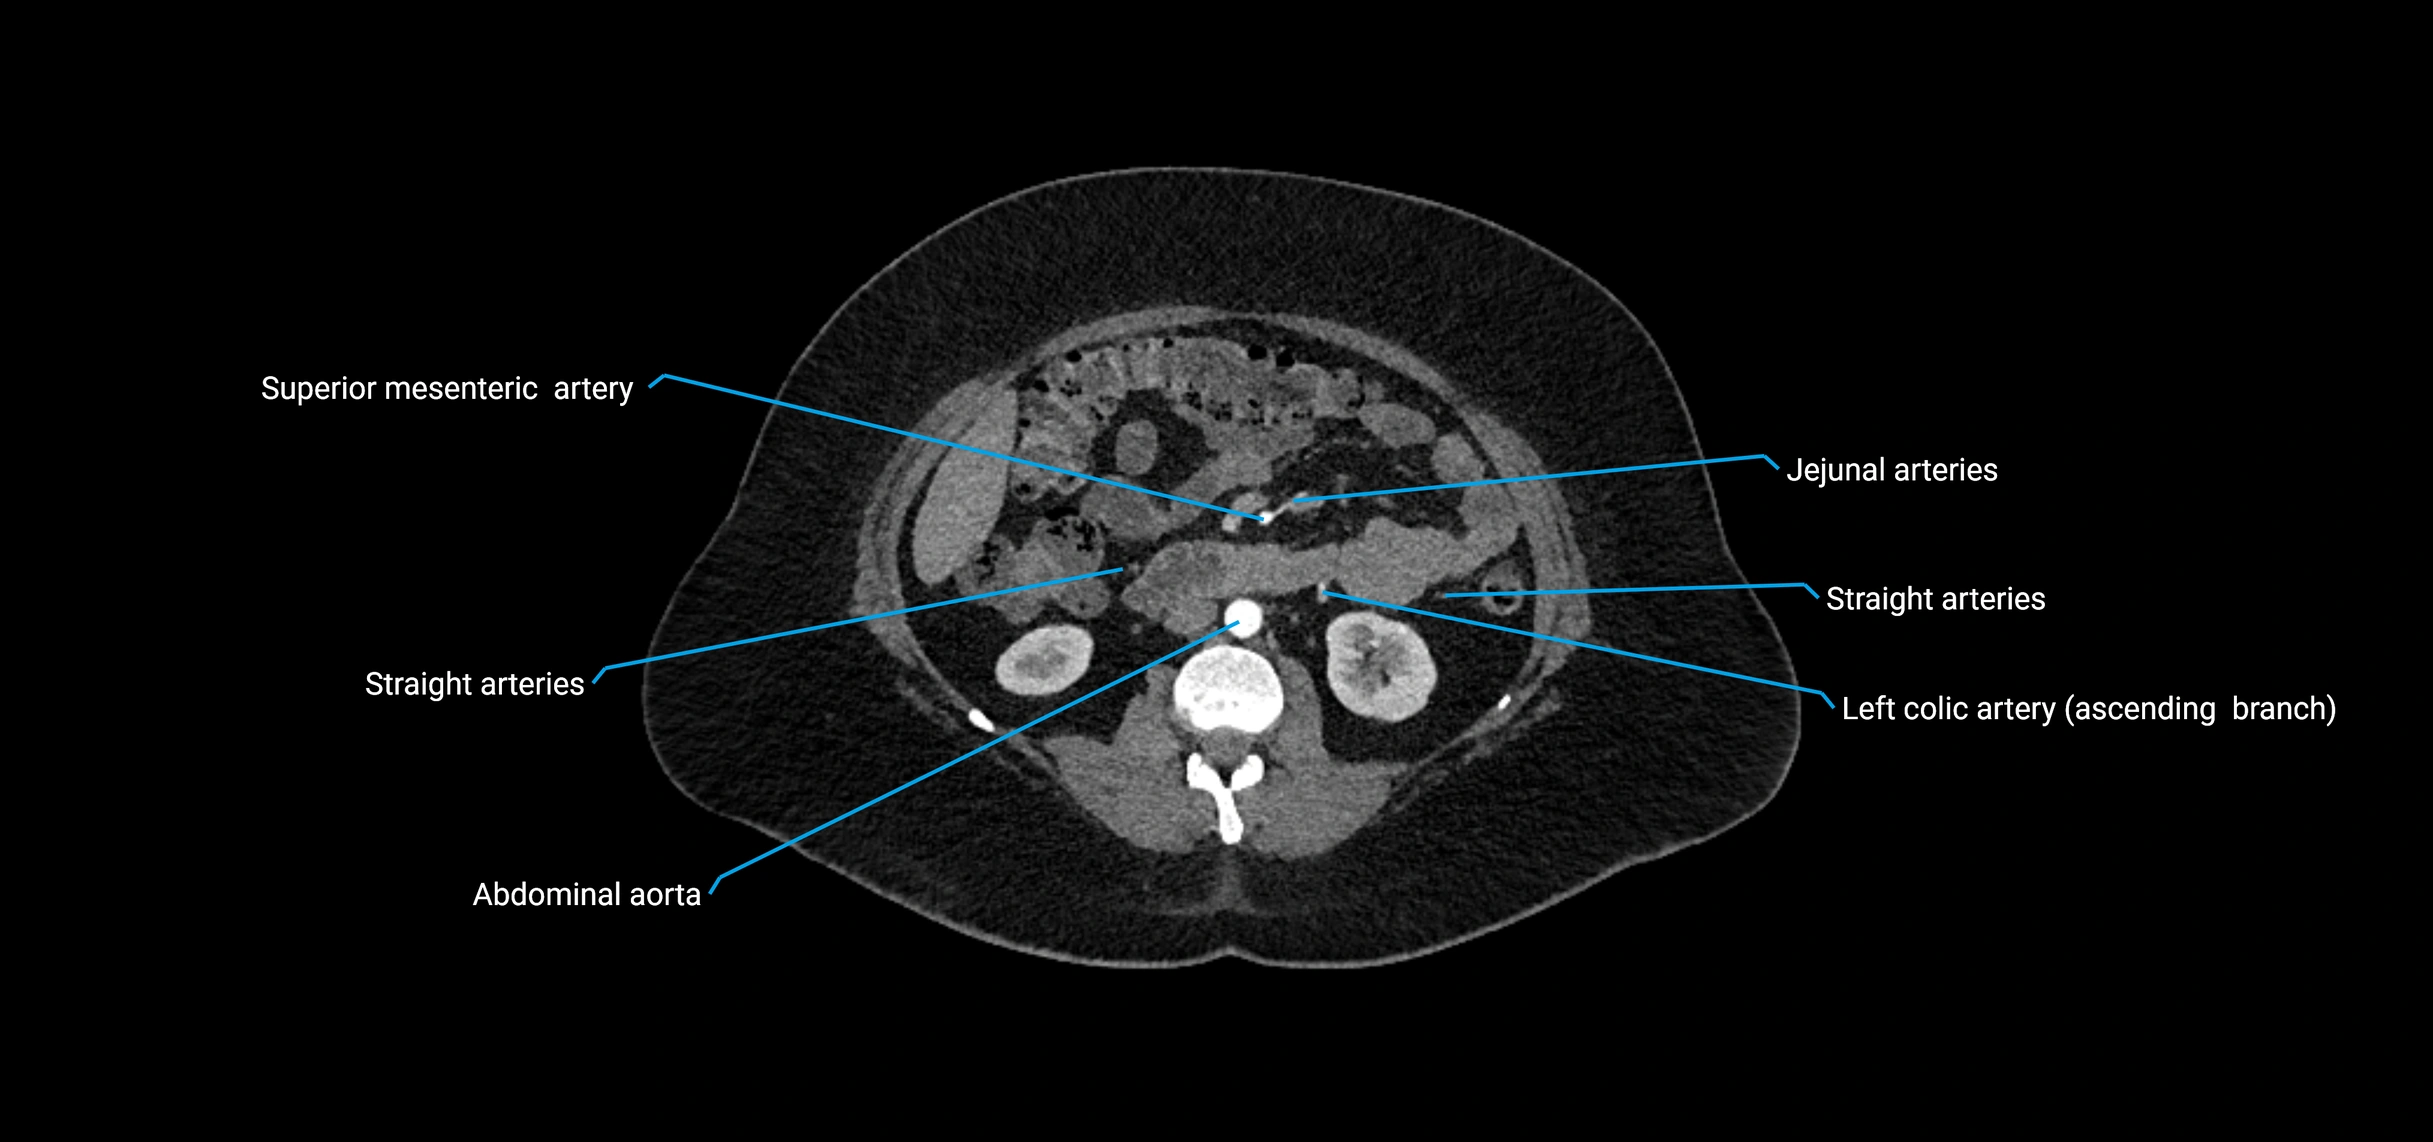

CT Appearance

Non-contrast CT:

• Appears as a tubular soft tissue structure anterior to vertebral bodies

• Calcified atherosclerotic plaques appear as hyperdense foci along the wall

• Useful for screening abdominal aortic aneurysm (AAA) size and mural calcification

Contrast-enhanced CT (CTA):

• Gold standard for abdominal aortic imaging

• Provides excellent detail of lumen, wall, aneurysm, thrombus, and branch vessels

• Multiplanar and 3D reconstructions help in aneurysm measurement, stent graft planning, and dissection evaluation

• Detects acute rupture, traumatic injury, or occlusion with high sensitivity

CT images

image